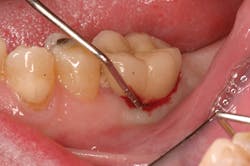

Late implant complications occur after the implant has integrated and the final prosthesis has been placed. Recognition of these complications via radiographic and clinical analysis is extremely important since many of these problems can be corrected if detected early. On the other hand, if allowed to progress, a minor complication can often result in loss of the implant and/or prosthesis. Late complications of the dental implant fall into the category of biologic or mechanical complications. Late biologic complications are those in which the peri-implant soft and hard tissues are affected. Peri-implant mucositis describes a reversible inflammatory reaction in the mucosa adjacent to an implant,(8) a term that has become known as implant gingivitis. Studies show that the prevalence of peri-implant mucositis can be as high as 50% to 80% of implants in function(9) with the etiology of peri-implant mucositis being bacterial plaque. Typical clinical presentation includes erythema, edema, swelling, and redness (Figs. 1 and 1a). Although bleeding upon probing and increased probing depths are not always indicative of peri-implant mucositis,(10) the absence of these two factors usually means implant health.(11)